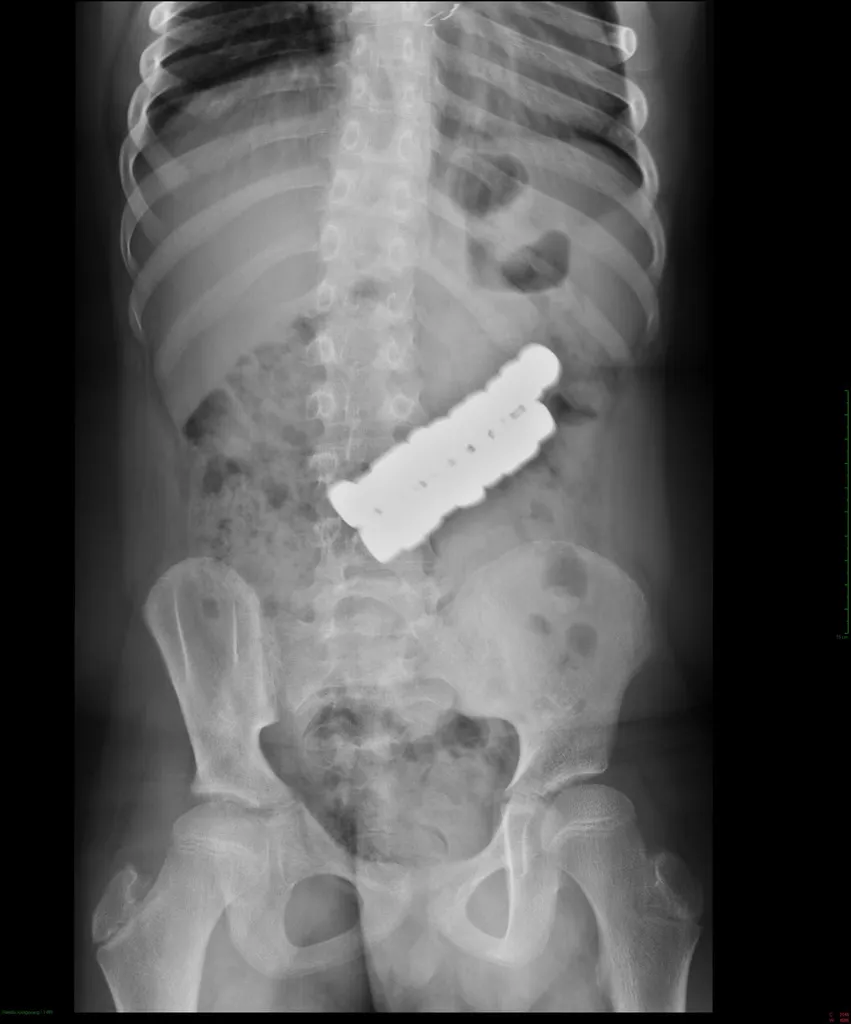

A kisfiú egy társasjátékhoz tartozó 20 darab mágnest nyelt le, ami végül komoly orvosi beavatkozást tett szükségessé. A Heim Pál Országos Gyermekgyógyászati Intézet orvosai először endoszkópos úton próbálták eltávolítani az idegen testeket, azonban a mágnesek erőssége és tömege miatt ez nem volt sikeres, így nem tudták elkerülni a műtétet. A kisfiú valószínűleg közvetlenül egymás után nyelhette le az elemeket, mert a mágnesek egyben, összekapcsolódva helyezkedtek el a gyomrában.

Ilyenkor előfordulhat, hogy a mágnesek a bélrendszer különböző szakaszaiban helyezkednek el és egymáshoz tapadhatnak a bélszakaszokon keresztül, közéjük szorulhat a bélfal. Ez akadályozza a vérkeringést, ami szövetelhaláshoz és akár a bél kilyukadásához vezethet. Szerencsére most nem ez történt, de így is műtétre volt szükség.